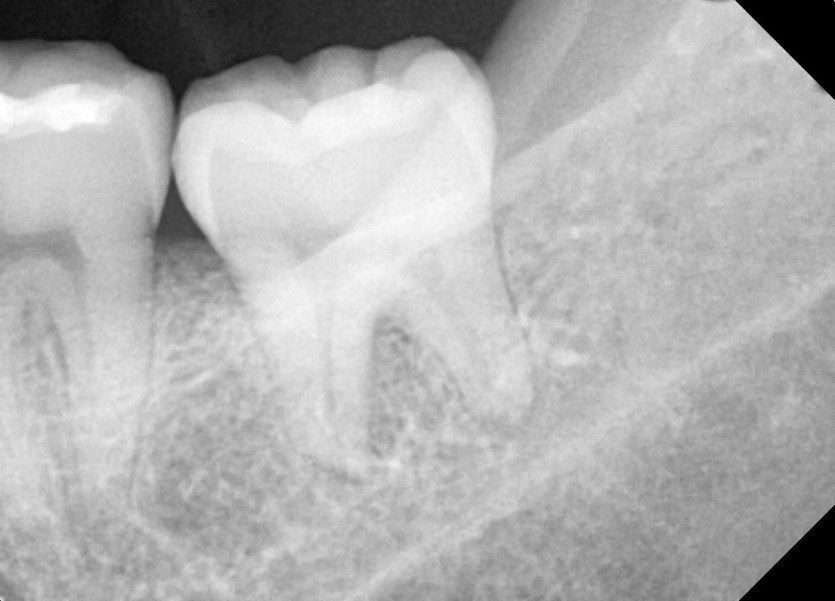

#28,38 사랑니 발치

구강외과 전문의가 당일 발치했습니다.